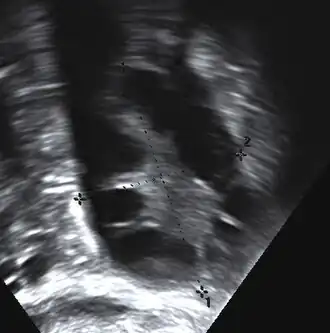

The syndrome acquired its most widely used name due to the common sign on ultrasound examination of multiple (poly) ovarian cysts. These "cysts" are immature ovarian follicles. The follicles have developed from primordial follicles, but this development has stopped ("arrested") at an early stage, due to the disturbed ovarian function. The follicles may be oriented along the ovarian periphery, appearing as a 'string of pearls' on ultrasound examination.[63]

Gynecologic ultrasonography first looks for small ovarian follicles.[75] To count as polycystic ovaries, at least 20 follicles need to be present, smaller than 9 mm. This used to be 12 in older diagnostic criteria.[16] A less clear marker of PCOS is enlarged ovaries.[75] Ovary need to be at least 10 cm3 to count.[16] For sexually active individuals or those that agree, a transvaginal ultrasound approach is preferred. Alternatively, AMH levels can be tested in the blood.[75] Laparoscopic examination may reveal a thickened, smooth, pearl-white outer surface of the ovary. This would usually be an incidental finding if laparoscopy were performed for some other reason, as it would not be routine to examine the ovaries in this way to confirm a diagnosis of PCOS.[78]